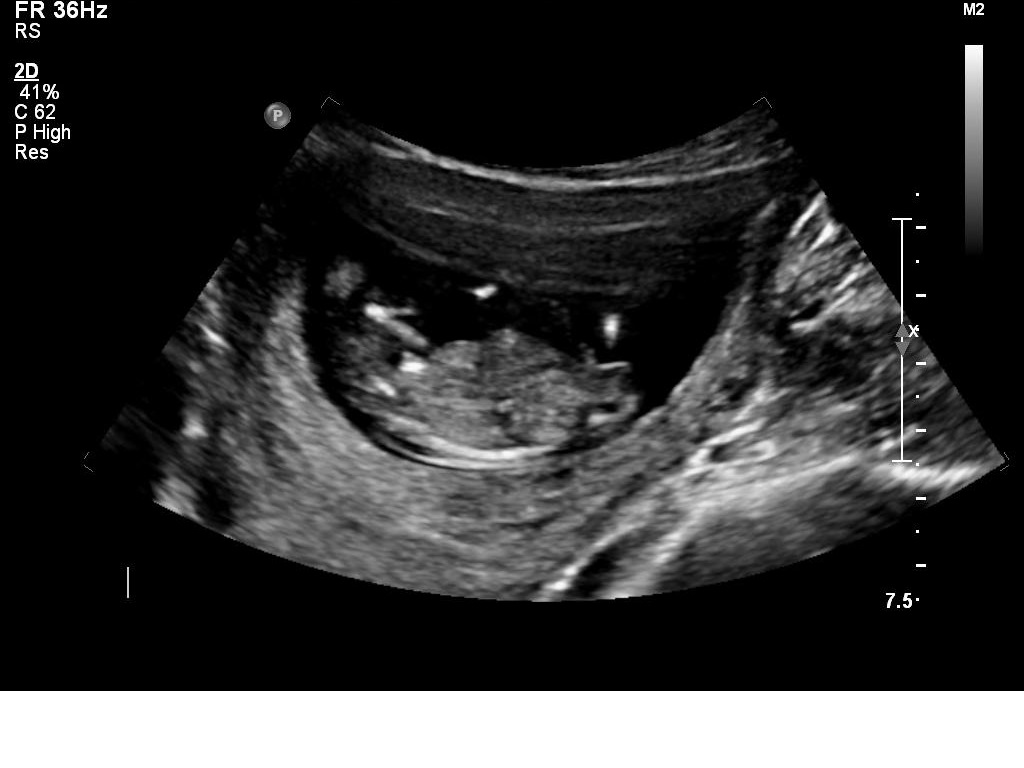

I had my 12w1d ultrasound today, but baby measured ahead at 13 weeks. Bub was very uncooperative and made it hard for the technician to get the NT measurements, which was good in a way because I got to see lots of bub! We got heaps of pictures and I will upload a few here.

I *think* I can tell the gender by the nub pictures but I'd love lots of guesses!!

What do you all think?